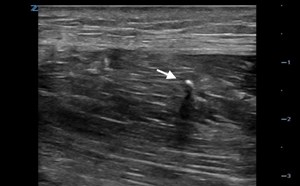

- The tip of the needle is seen as a hyperechoic structure entering through the abdominal wall into the fluid and steering clear of the moving bowel and the bladder, especially with the infra-umbilical approach.